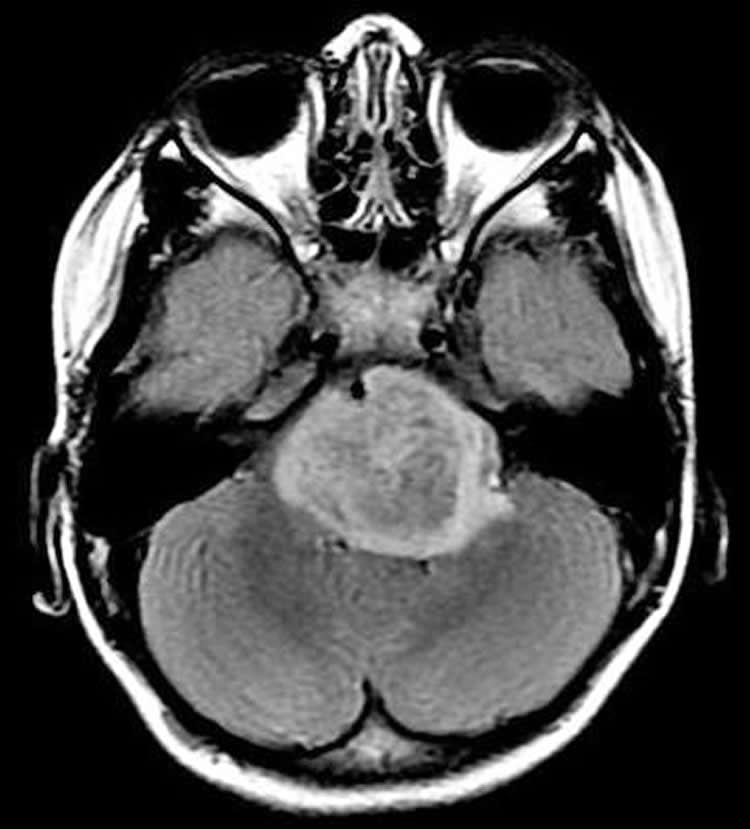

DIPG typically attacks children 4 to 9 years of age. Children progressively lose muscle control as the tumor rapidly attacks the pons, a region deep inside the brain that connects the brain to the spinal cord, and is difficult to reach and surgically remove. Despite radiation treatment, children usually survive for about nine months, and less than 1 percent survive longer than five years.

Image Source: The image is credited to Monje lab, Stanford University, CA